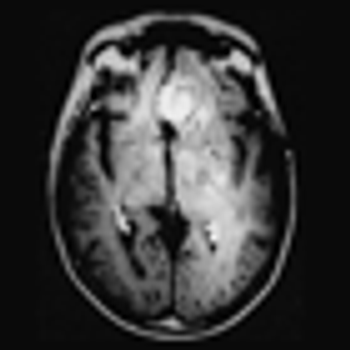

A genomic analysis of the primary tumors and brain metastases of patients has revealed potentially targetable mutations only present in the brain metastases.